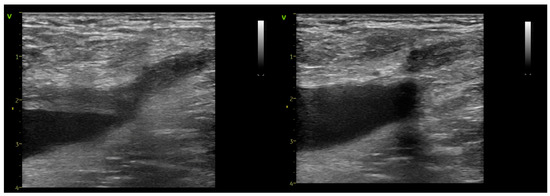

Assessing Endovenous Heat-Induced Thrombosis in Flush Endovenous Laser Ablation: A Study on Incidence, Risk Factors, and Patient Outcomes

J. Clin. Med. 2025, 14(17), 6165; https://doi.org/10.3390/jcm14176165 - 31 Aug 2025

Introduction: The introduction of radial-firing laser fibers has minimized catheter-to-vein distance during endovenous laser ablation (EVLA) for the great saphenous vein (GSV) and anterior saphenous veins (ASVs). This study investigates flush endovenous laser ablation (fEVLA) effectiveness in addressing chronic superficial venous insufficiency (CVI). [...] Read more.

Introduction: The introduction of radial-firing laser fibers has minimized catheter-to-vein distance during endovenous laser ablation (EVLA) for the great saphenous vein (GSV) and anterior saphenous veins (ASVs). This study investigates flush endovenous laser ablation (fEVLA) effectiveness in addressing chronic superficial venous insufficiency (CVI). Materials and methods: This single-center retrospective study analyzed consecutive fEVLA cases with duplex ultrasound follow-up at 1, 4, and 12 weeks. The primary endpoint was clinically significant endovenous heat-induced thrombosis (classes III–IV). Results: Three hundred and twelve patients were recruited (405 affected limbs, 369 GSV, and 36 ASV). CEAP classifications were stratified as follows: C2 in 6.1%, C3 in 34.2%, C4 in 44%, C5 in 2.7%, and C6 in 12.7% of cases. Perforator ligation, phlebectomy, or foam sclerotherapy were carried out in conjunction with EVLA. fEVLA was feasible in all cases. The success rate was 96.78%, defined as EHIT classes 1 and 2, and assessed by ultrasound one week postoperatively. Clinically significant EHIT (2.5% class 3 and 0.2% class 4) was managed with 15 mg rivaroxaban twice daily for 21 days. Follow-up at 4 weeks revealed complete resolution of all EHIT 3–4 cases. No cases of pulmonary embolism or deep vein thrombosis were observed during the study or follow-up period. Conclusions: fEVLA is a safe treatment for superficial CVI across various CEAP classes, and with prompt detection, the minimal complication rate can be completely resolved. Full article

Show Figures

Figure 1